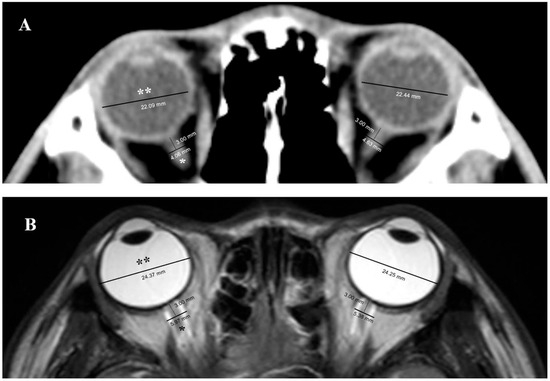

2.4. Measurement of ONSD and ETD in Brain CT and MRI